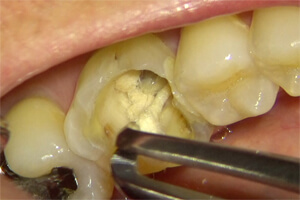

6

虫歯を除去し再度バイ菌が入らないよう壁を作ると痛みは無くなりました。(隔壁と言います)